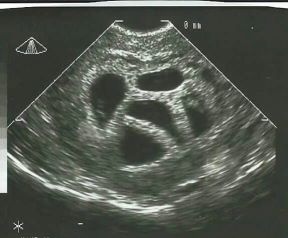

Zatrudnjela s petorkama, liječnici savjetovali smanjenje fetusa: 20 godina kasnije pokazala ovu fotku

uzv5.jpg

Trudnoća

Imate visokorizičnu trudnoću? Tri stručnjakinje otkrile što žele da svaka trudnica zna